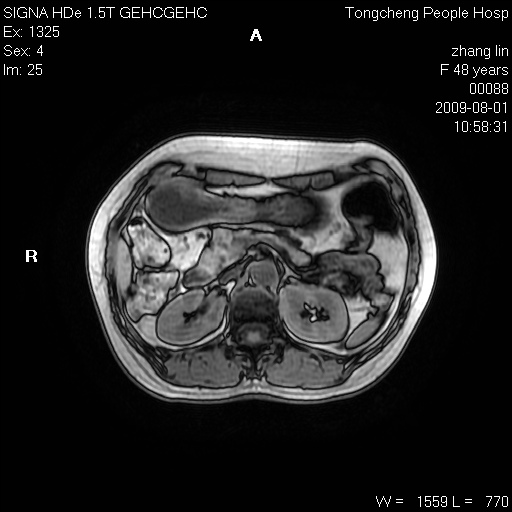

女,48岁。健康体检,彩超发现右肾占位性病变。平素健康。

临床诊断:右肾占位性病变,性质待定(囊肿?肿瘤?)。

上中腹部mr平扫+增强扫描,图像如下:

右肾上极见一类圆形病灶,t1wi呈等信号t2wi呈等高混杂信号,三期增强无强化,边界清---考虑囊肿出血。

同反相位均表现为等信号,病变无强化,考虑含蛋白的囊肿可能,弥散加权相或许有些帮助,

肝囊肿

慢性胆囊炎